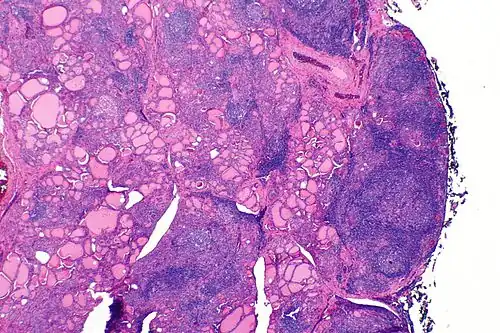

| A micrograph of the thyroid of someone with Hashimoto's thyroiditis | |

Gross morphological changes within the thyroid are seen in the general enlargement, which is far more locally nodular and irregular than more diffuse patterns (such as that of hyperthyroidism). While the capsule is intact and the gland itself is still distinct from surrounding tissue, microscopic examination can provide a more revealing indication of the level of damage.[55] Hypothyroidism is caused by replacement of follicular cells with parenchymatous tissue.[52]

Pathology

Gross pathology of a thyroid with autoimmune thyroiditis may show a symmetrically enlarged thyroid.[5] It is often paler in color, in comparison to normal thyroid tissue, which is reddish-brown.[5]

Microscopic examination (histology) will show lymphocytes (including plasma B-cells) diffusely infiltrating the parenchyma.[55] The lymphocytes are predominately T-lymphocytes with a representation of both CD4+ and CD8+ cells.[5] The plasma cells are polyclonal, with present germinal centers resembling the structure of a lymph node[5] (also called secondary lymphoid follicles, not to be confused with the normally present colloid-filled follicles that constitute the thyroid).[55]

In late stages of the disease, the thyroid may be atrophic.[10] Colloid-filled follicles shrink, and the cuboidal cells that usually line the follicles become Hürthle cells.[5] Fibrous tissue may be found throughout the affected thyroid as well.[5] Severe thyroid atrophy presents often with denser fibrotic bands of collagen that remain within the confines of the thyroid capsule.[55]

Generally, pathological findings of the thyroid are related to the amount of remaining thyroid function — the more infiltration and fibrosis, the less likely a patient will have normal thyroid function.[5] A rare but serious complication is thyroid lymphoma, generally the B-cell type, non-Hodgkin lymphoma.[24]